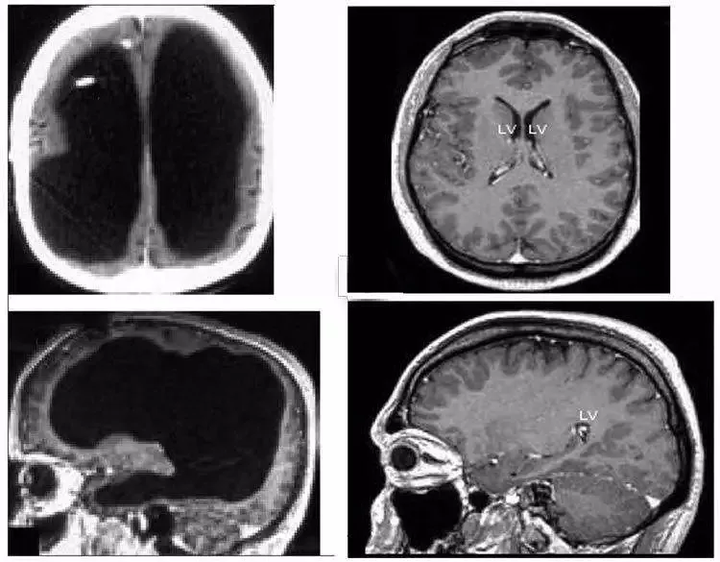

2007 年,《柳叶刀》上的一篇论文,展示了一个非常惊人的案例[1]。

1 位 44 岁的法国男子,大脑被脑脊液压缩得仅有薄薄一层:

这如同纸一样薄的大脑皮层,已经看不出什么沟回。

虽然他的智商测试仅有 75,但依旧还算不上智力障碍(IQ≤70 分为临界值)。